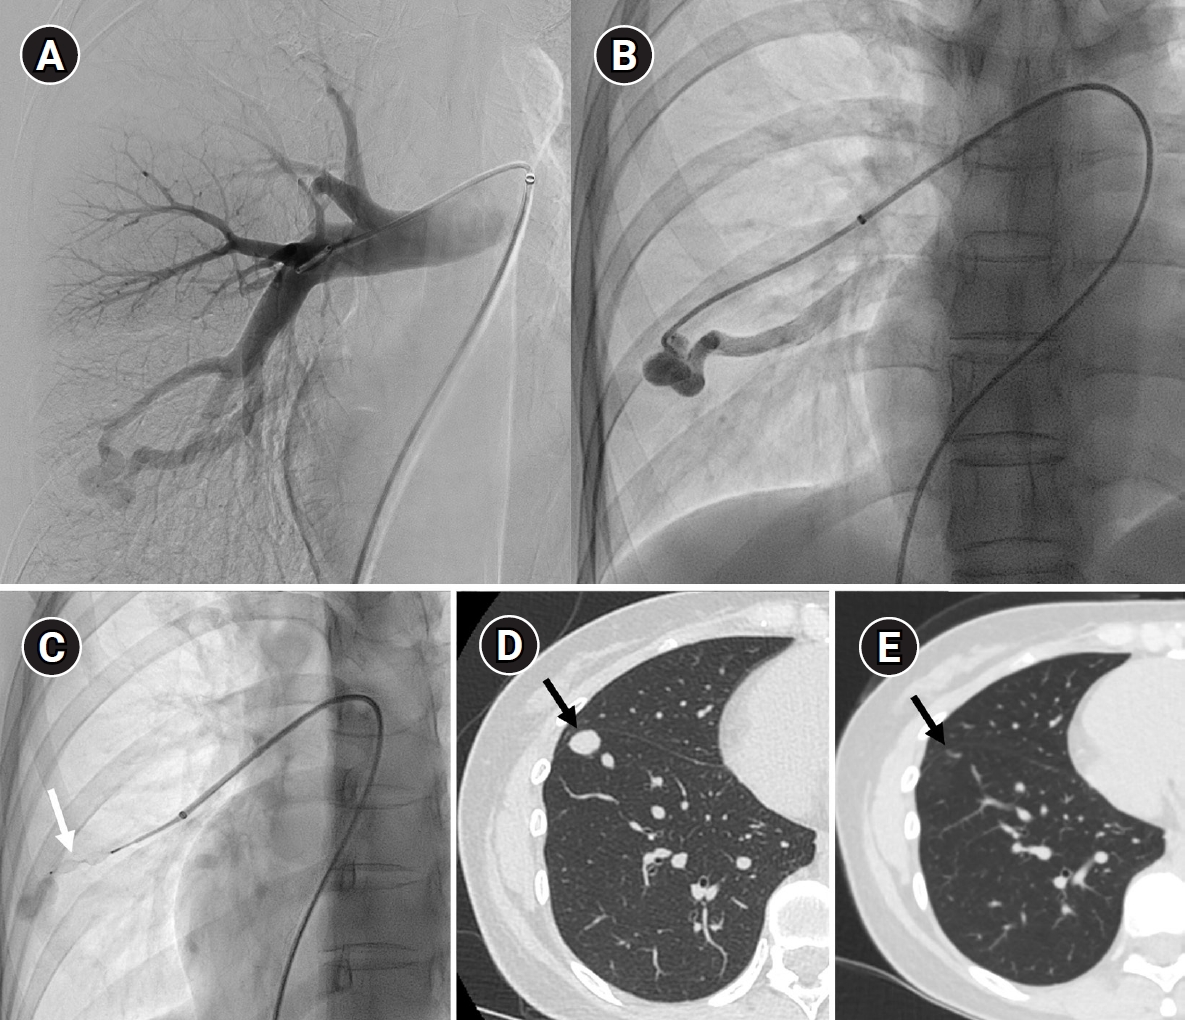

Fig. 4.

The images show a 38-year-old female patient undergoing pulmonary arteriovenous malformation embolization using an Amplatzer vascular plug. (A) A simple pulmonary arteriovenous malformation is observed in the right pulmonary angiography, and the feeding artery diameter is measured at 3.7 mm. (B) An 8-Fr, 80-cm guiding catheter and a 5-Fr Berenstein angled catheter were used to advance to the distal end of the feeding artery. (C) A 7-mm Amplatzer vascular plug type IV (arrow) was deployed at the distal portion of the feeding artery with a 100% oversizing. (D, E) The large venous sac (arrow) that was visible on the pre-procedure non-enhanced chest computed tomography (CT) (D) had only a trace remaining (arrow) on the CT performed 6 months later (E).

Fig. 4. The images show a 38-year-old female patient undergoing pulmonary arteriovenous malformation embolization using an Amplatzer vascular plug. (A) A simple pulmonary arteriovenous malformation is observed in the right pulmonary angiography, and the feeding artery diameter is measured at 3.7 mm. (B) An 8-Fr, 80-cm guiding catheter and a 5-Fr Berenstein angled catheter were used to advance to the distal end of the feeding artery. (C) A 7-mm Amplatzer vascular plug type IV (arrow) was deployed at the distal portion of the feeding artery with a 100% oversizing. (D, E) The large venous sac (arrow) that was visible on the pre-procedure non-enhanced chest computed tomography (CT) (D) had only a trace remaining (arrow) on the CT performed 6 months later (E).

Historically, detachable balloons were used as an embolization material; however, they are no longer utilized in current practice [18]. In the context of PAVM embolization, the use of coils, vascular plugs, or a combination of both is now standard practice [19-21]. Since the development of detachable coils, they have offered advantages over pushable coils, particularly in terms of repositioning during the procedure. They can even be fully retrieved and redeployed if necessary, enhancing procedural safety and control. It is crucial to prioritize minimizing the recanalization rate while ensuring the overall safety of the procedure when selecting the appropriate embolic materials and techniques. Feeding artery coil embolization was historically regarded as the standard approach, whereas venous sac embolization was discouraged because of the perceived risk of rupture [22]. However, with the introduction of newer venous sac embolization techniques, recent findings now indicate that tightly packing the venous sac with coils can achieve a higher success rate than the traditional feeding artery approach (Fig. 2) [22-25]. Additionally, vascular plugs, including micro-vascular plugs (Medtronic, Minneapolis, MN, USA) and Amplatzer vascular plugs (Abbott Vascular, Saint Paul, MN, USA) have also demonstrated a higher success rate compared to feeding artery coil embolization (Fig. 4) [26-28]. In the case of vascular plugs, the risk of device migration is relatively low. Moreover, an additional advantage is that the device can be repositioned if the sizing is not ideal or if it is not deployed in the exact desired location. This flexibility enhances the precision of the procedure (Fig. 5). In a recent European guideline, there is also a recommendation to consider vascular plug embolization as a first-line option whenever possible, rather than coil embolization [11]. Additionally, a recent meta-analysis recommended vascular plugs or venous sac coil embolization, noting that vascular plugs had a recanalization rate of 13.6% compared to 32.7% for coil-only embolization. Similarly, venous sac embolization showed a 3.8% recanalization rate, while feeding artery embolization had a rate of 24.3%. Additionally, a recent meta-analysis has recommended the use of vascular plug or venous sac coil embolization, as these techniques have demonstrated a lower persistence rate compared to other methods [21]. This shift is largely in response to the relatively high recanalization rate associated with feeding coil embolization. In the case of embolization using vascular plugs, the plug should be deployed at the most distal segment of the feeding artery just before the venous sac in order to preserve the normal pulmonary artery. Since the pulmonary artery contains less elastin and has a thinner wall compared to systemic arteries, it is more distensible [29]. Therefore, in the author's experience, oversizing by about 50% to 100% has been effective in reducing the recanalization rate. When performing venous sac coil embolization, it is important to use coils large enough to create a stable framing coil larger than the draining vein diameter, thereby preventing coil migration. After establishing this frame, the venous sac and the proximal feeding artery should be carefully packed to achieve complete occlusion.